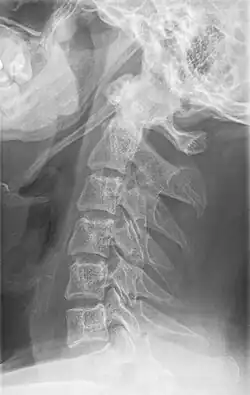

Radiograph, lateral view showing elongated stylohyoid process and stylohyoid ligament ossification -

Imaging is important and is diagnostic. Visualizing the styloid process on a CT scan with 3D reconstruction is the suggested imaging technique.[13] The enlarged styloid may be visible on an orthopantogram or a lateral soft tissue X ray of the neck.